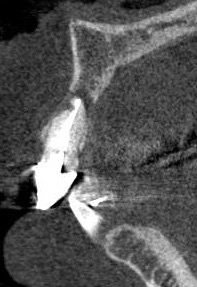

中学生の時に、歯をぶつけたようです。 内部吸収をおこしていました。